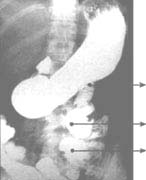

El paciente fue dado de alta el día 250 de hospitalización, con diagnóstico de intestino corto para manejo ambulatorio. El remanente intestinal es de 12,5 cm de duodeno, 3-4 cm de íleon terminal y todo el colon (Figura 1).

Duodeno

Ileon Colon;

Figura 1. Control postoperatorio con medio de contraste.